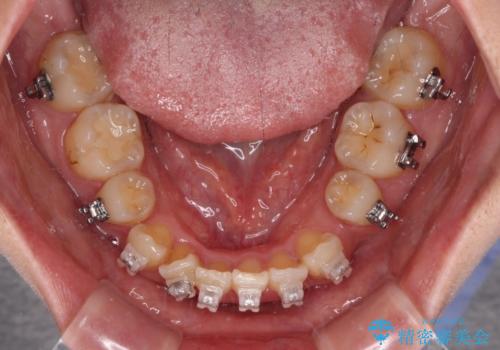

- 海外で抜歯矯正を開始し、治療途中で帰国したため、転院先を探しているとのことで来院された患者様です。

ワイヤーは抜けてしまい、後戻りが始まっている状態でしたが、既存の装置を継続利用して受け入れてくれる医院が見つからないとのことでした。

当院では、張り替える必要のある部位は張り替えることで継続することとし、抜歯スペースを閉じていくように治療を行うこととしました。